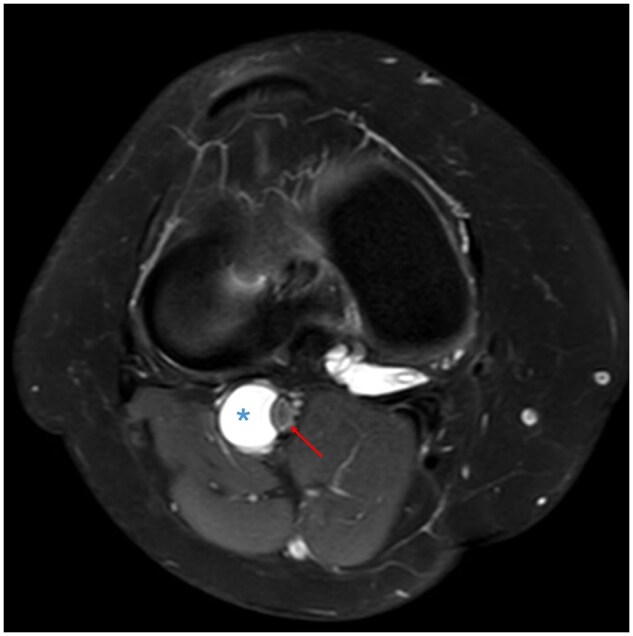

囊性外膜病是一种罕见的小腿跛行原因,其特征是在动脉外层(外膜)内发生粘液囊性肿块。腘动脉最常受影响。关于这种疾病的病因存在几种理论和假设,迄今为止文献中没有明确的统一原因。我们描述了一个32岁的女性病例,她有一年的右膝内侧疼痛和间歇性跛行史,她被诊断为内侧半月板撕裂和一个与腘动脉外膜相连的大腹膜旁囊肿。她接受了关节镜半月板切除术和囊肿减压,并获得了良好的功能结果,跛行得到了解决。

Cystic adventitial disease is a rare cause of calf claudication and is characterized by the development of a mucinous, cystic mass within the outer layer (adventitia) of an artery. The popliteal artery is most commonly affected. Several theories and hypotheses exist regarding the aetiology of this disorder with no clear unifying cause accepted in the literature to date. We describe a case of a 32-year-old female with a one-year history of medial right knee pain and intermittent claudication who was diagnosed with a medial meniscal tear and a large parameniscal cyst communicating with the popliteal artery adventitia. She underwent arthroscopic meniscectomy and cyst decompression and achieved an excellent functional outcome with resolution of the claudication.